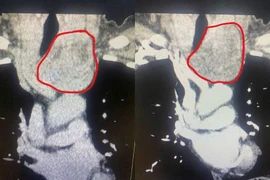

Human Papiloma virus (HPV) gây u nhú thanh quản

Ho kéo dài do u nhú thanh quản

U nhú thanh quản là một tổn thương lành tính ở thanh quản. Trẻ em gặp nhiều hơn ở người lớn, gặp nhiều lứa tuổi 2 – 5 tuổi và 20 – 40 tuổi.